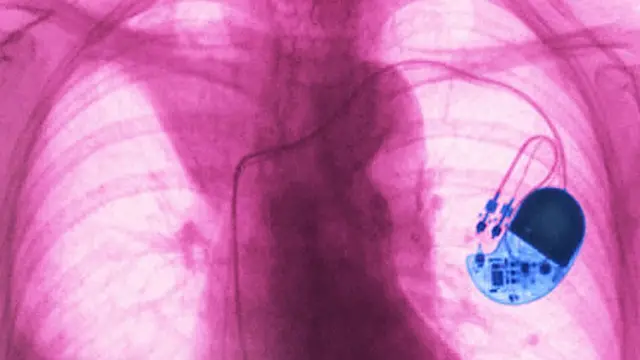

يشكل جهاز تنظيم ضربات القلب الجاري استخدامه حاليا معجزة طبية، فبإمكانه إرسال نبضات كهربائية لقلب الإنسان، كي يواصل الخفقان بشكل منتظم، رغم أن حجمه لا يتجاوز حجم علبة الثقاب.

وتفيد الإحصاءات بأن العالم يشهد سنويا تركيب 1.25 مليونا من هذه الأجهزة، التي تؤدي الاستعانة بها لأن يشعر من يعانون من اضطراب في ضربات القلب، بتحسن كبير في "نوعية" حياتهم، كما يعيد ذلك متوسط الحياة المتوقع لبعض الأشخاص، إلى معدلاته المعتادة.

ومع أن هذا الجهاز تطور بشكل مطرد على مدار العقود الماضية - تحديدا منذ أن تم تركيب أول نموذج منه قابل للزرع بشكل كامل في جسم الإنسان عام 1958 - فإن الفكرة الرئيسية التي تقف وراء عمله لم تتغير. فالأقطاب الكهربائية المزروعة في إطاره، تراقب نبضات قلبك، وحينما تجد أنها باتت تتسم بطابع غير مألوف، يصدر الجهاز نبضات كهربائية تحفز عضلات القلب على الانقباض، حتى تواصل ضخ الدم لمختلف أنحاء الجسم.

ويتولى هذا الجهاز ضمان أن يواصل قلبك نبضه بإيقاعه المعتاد نفسه في كل الحالات، سواء كنت نائما أو حتى مشاركا في سباق للماراثون.